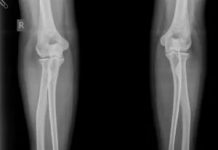

В каких случаях нужно делать рентген локтя?

Рентгенологическое исследование локтевого сустава обычно проводится в случае его травмы. В области локтя прикрепляются мышцы, участвующие как в выпрямлении, так и в сгибании предплечья,...